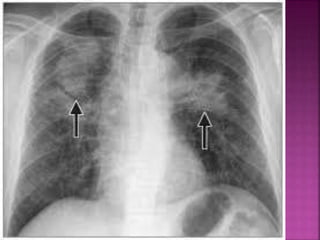

 Chest x-ray findings include small irregular

opacities, interstitial densities, ground glass

appearance, and honeycombing.